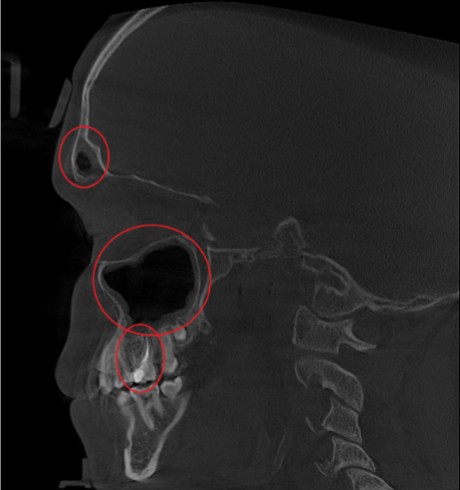

Проведена компьютерная томография околоносовых пазух, которая подтвердила наличие правостороннего гемисинусита (воспаление нескольких пазух с одной стороны), как следствие периодонтита зуба 1.6.

Представлено КЛКТ околоносовых пазух до начала лечения. Выделена зона воспаления пазух.

На снимке детально представлена область пораженного зуба 1.6.